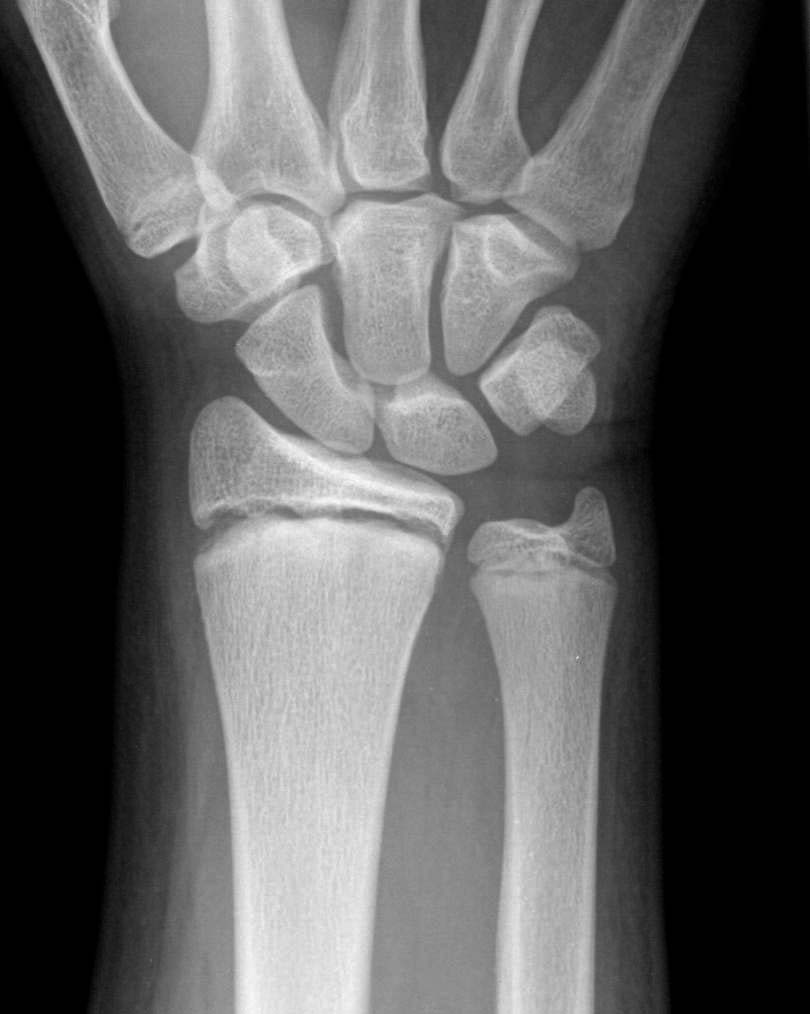

Wrist Fracture Xrays YouTube

Distal Radius Fracture Raleigh Hand Surgery — Joseph J. Schreiber, MD Fracture X Ray Quiz blood under skin after a fracture. Study with quizlet and memorize flashcards. You have 10 seconds to identify the fracture. Keep in mind that it is often not. study with quizlet and memorize flashcards containing terms like what is it called when you follow the compact bone or cortical. fracture descriptors depend on the class of bone. Fracture X Ray Quiz.

XRay wrist fracture. Download Scientific Diagram Fracture X Ray Quiz the test yourself scenarios below are based on the objective structured clinical examination (osce) style assessments. Study with quizlet and memorize flashcards. Decrease in bone mineral density. Describe which bone is involved and where the fracture is located (proximal/middle/distal). fracture descriptors depend on the class of bone and the direction of the fracture line. Keep in mind that. Fracture X Ray Quiz.

Fractured Wrist X Ray Fracture X Ray Quiz Decrease in bone mineral density. 159 rows litfl 100 (150) cxr quiz. the test yourself scenarios below are based on the objective structured clinical examination (osce) style assessments. Study with quizlet and memorize flashcards. Answers follow directly after the quiz. fracture descriptors depend on the class of bone and the direction of the fracture line. study. Fracture X Ray Quiz.